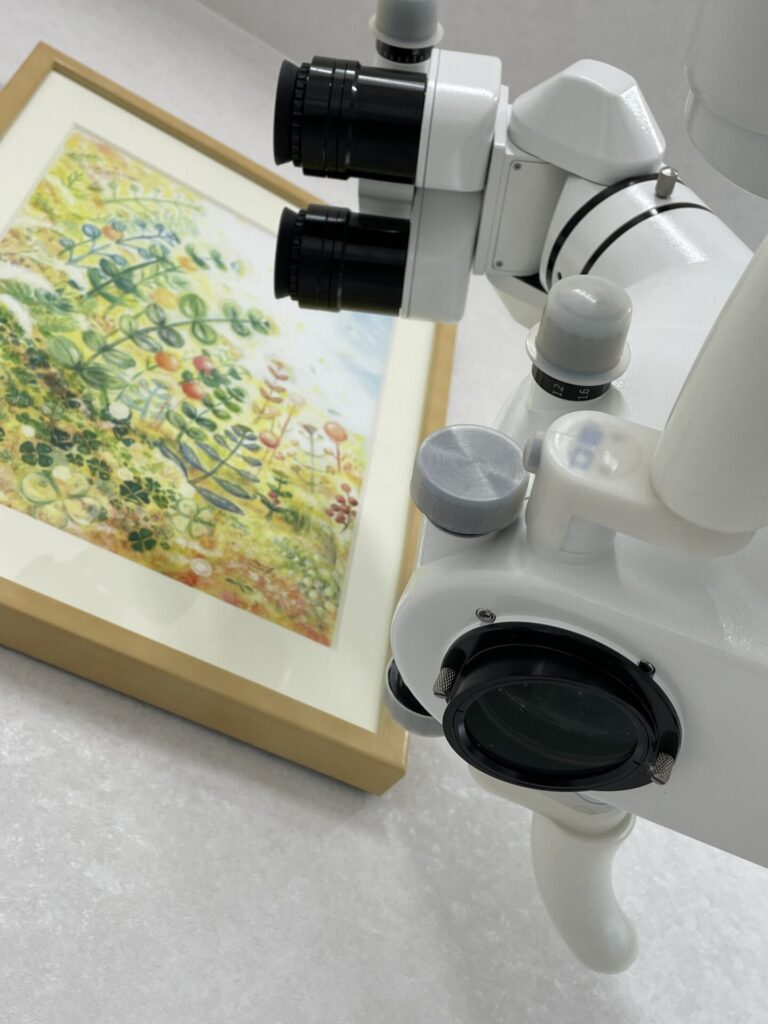

ラバーダム防湿を行い、マイクリスコープ下での治療です。近心の根には2つの根管があります。この第2根管は裸眼の治療では高頻度で見落とされる傾向にあります。CTを事前に撮影しておくことで複雑な歯の神経の道を事前に把握することは非常に重要です。